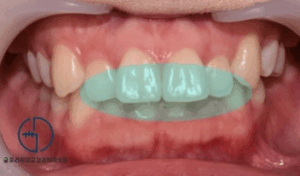

상봉역 교정치과 앞니 벌어짐 발치 교정 및 왜소치 라미네이트 과정

안녕하세요, 상봉역 교정치과 김정은 원장입니다. 왜소치에 대해 들어보신적 있으신가요? 왜소치는 말그대로 정상적인 치아크기보다 작게 형성된 이를 말합니다, 특히 앞니 부위에서 흔히 나타나며 치아 사이 공간이 남거나 비율이 어색해보이는 심미적 고민으로도…